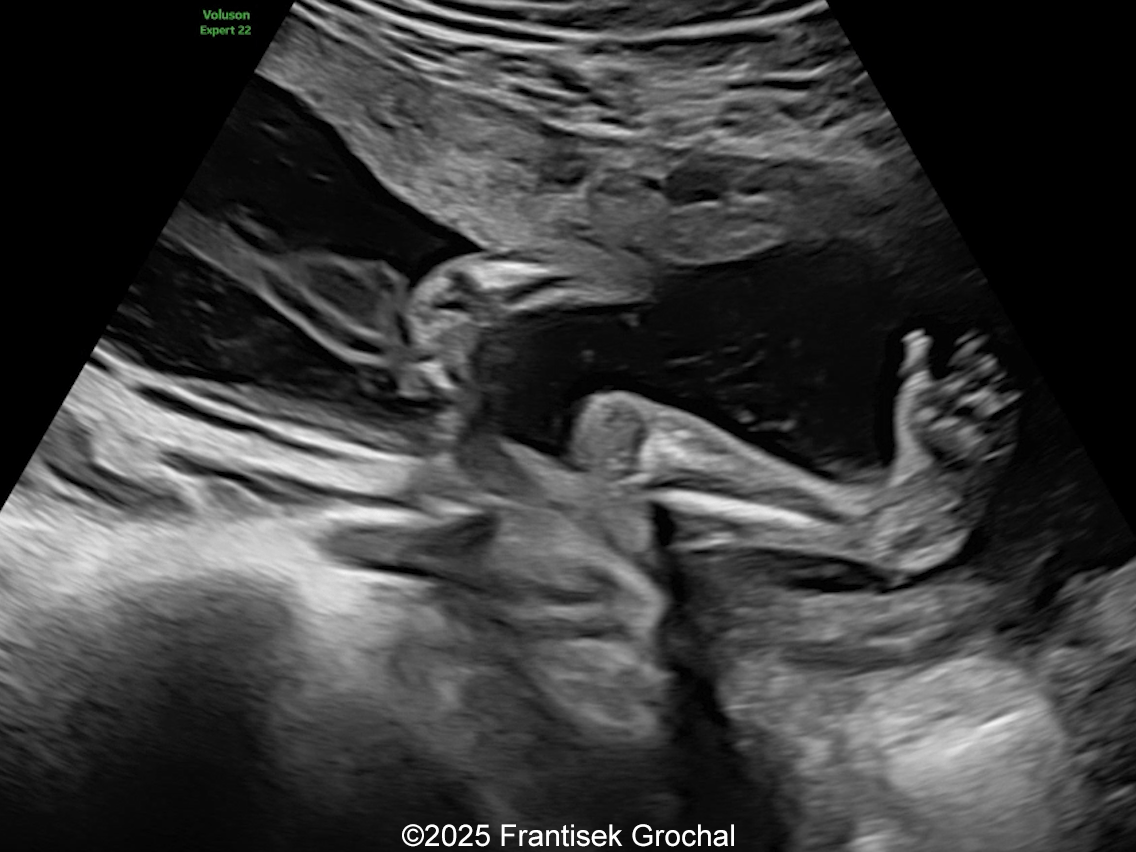

We present a case of Amniotic Band Sequence seen in 21st week of pregnancy. The fetus showed the following findings:

- Bilateral club feet

- Constriction of fetal torso by two strips of amniotic band

Prenatal ultrasound imaging shows thin echogenic bands attaching to both the uterine wall and associated fetal structures. The bands themselves can be difficult to detect, hence the visualization of bands is not required to suggest the diagnosis. Random anomalies that do not follow a pattern should lead the clinician to suspect amniotic band sequence and prompt close evaluation for a causative band [5, 6]. The defects resulting from the bands are categorized into various categories: neural tube-like defects, craniofacial anomalies, limb anomalies, abdominal and thoracic wall defects, and visceral anomalies [7, 8]. The most common findings are those caused by constriction rings in the limbs, which are present in at least 80% of cases. They may vary in depth, involving only the skin, to involving bone and causing edema of the distal limb, extremity asymmetry, pseudosyndactyly, or amputation of limbs or digits [8]. Histologically, constriction bands are composed of fibrous tissue containing fibroblasts covered by squamous cells, which may make them inelastic and produce a ligature effect [9]. Clubfoot deformity of the lower extremity is found in up to one third of cases, probably secondary to the presence of oligohydramnios if there is loss of amniotic fluid [6].

Cases of amniotic band sequence manifesting as constriction rings in the trunk (thorax, abdomen, or pelvis) are exceedingly rare. They were first described as abdominal constriction syndrome by Browne in 1957 [9]. The consensus is that the cause of this finding is the presence of amniotic bands, although Lin et al [10] described a case they attribute to compression by the umbilical cord. To the best of our knowledge, constriction rings in the trunk have only been described prenatally on two occasions [11,12]. The diagnosis is usually made in the newborn after birth, although most of the published cases are patients treated during childhood. To unify terminology, Graham et al [11] propose defining thoracic constriction bands as those located between the clavicles and transpyloric plane, which passes through the vertebral body of L1. Abdominal constriction bands are located between the transpyloric and intertubercular planes (through the body of L5 and iliac tubercles), and pelvic constriction bands between the intertubercular plane and ischial tuberosities. As in the extremities, these bands occur at various depths, most commonly only to the fascial layer, but they can extend down to the external or internal oblique muscles [6]. Despite the “hourglass” appearance, abdominal bands do not seem to cause mechanical problems. In mild cases the ring may become less noticeable as the child grows, therefore most authors wait until the child is about a year of age before performing surgical correction [6]. This is typically performed with excision of fibrotic tissue and Z- or W-plasties to improve appearance and to allow expansion of abdominal contents [13, 14]. Prenatally, in cases where blood flow to the cord or a limb is compromised by amniotic bands, fetal surgery may be possible. The traditional open hysterotomy approach has been progressively replaced by fetoscopic methods, which reduce complications and the need to perform a cesarean section at the time of delivery. Prenatal treatment reduces scarring compared to procedures performed after birth, due to improved dermal remodeling in the maternal uterine environment [15, 16].